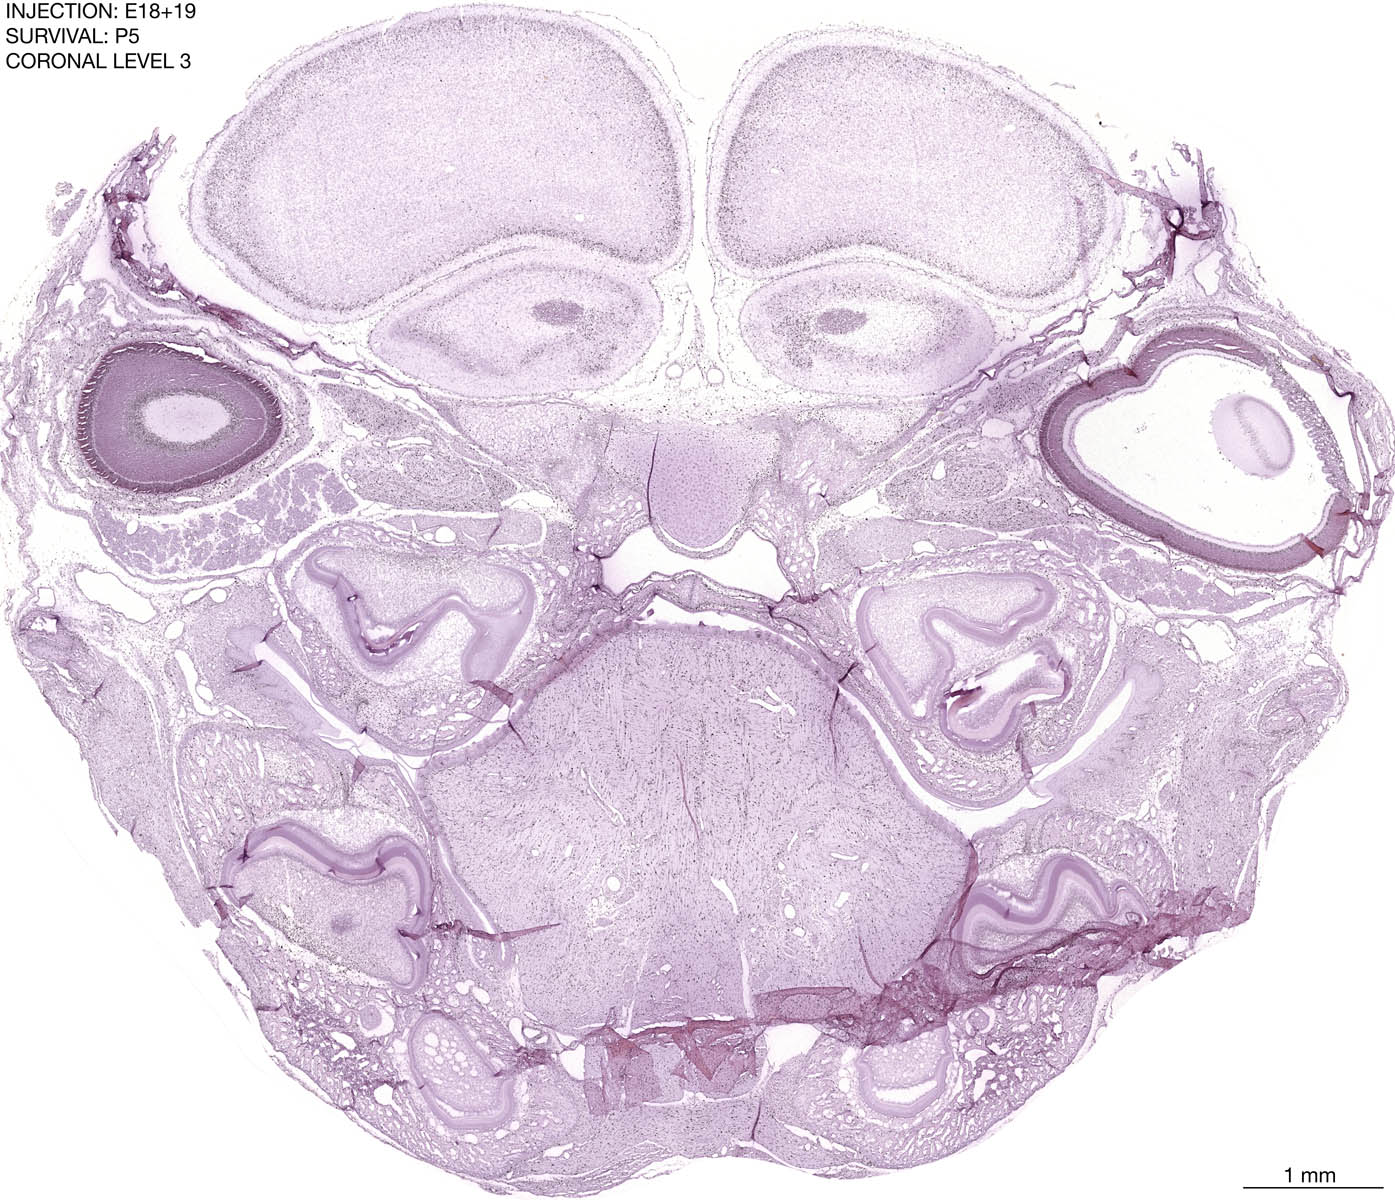

The images below are from the brain of a rat that was exposed to tritiated thymidine on E18+19 and survived to P5. Download: Large | High Res Download: Large | High Res Download: Large | High Res Download: Large | High Res Download: Large | High Res Download: Large | High Res Download: Large | High Res Download: Large | High Res Download: Large | High Res Download: Large | High Res Download: Large | High Res Download: Large | High Res Download: Large | High Res Download: Large | High Res Download: Large | High Res Download: Large | High Res Download: Large | High Res Download: Large | High Res Download: Large | High Res Download: Large | High Res Download: Large | High Res Download: Large | High Res Download: Large | High Res Download: Large | High Res